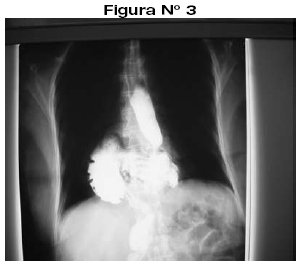

<body><![CDATA[<p align="justify"><font face="Verdana" size="2">Se trata de un paciente de 50 años de edad, de sexo femenino, que acude al servicio de diagnóstico por imágenes para exámenes radiológicos de rodillas, columna dorsolumbar y test de Farrel; observándose incidentalmente en la radiografía de columna imágenes de anormalidad y luego se indica radiografía de tórax PA y Lat. donde se observa imagen radioopaca con nivel hidroareo (<a href="#f12">Figura N&deg; 1,2</a>). </font></p>     <p align="justify"><a name="f12"></a></p>     <p align="center"><img src="/img/revistas/rmcmlp/v18n2/a06_figura_01.jpg" width="252" height="257"></p>     <p align="center">&nbsp;</p>     <p align="center"><img src="/img/revistas/rmcmlp/v18n2/a06_figura_02.jpg" width="293" height="239"></p>     <p align="justify"><font face="Verdana" size="2">Se complementa el mismo con un examen contrastado de esófago y estómago, observándose que el cardias, el estómago y parte del duodeno se hallan por encima del hiato o sea en la cavidad torácica. (<a href="#f3">Figura N&deg; 3</a>).</font></p>     <p align="justify"><a name="f3"></a></p>     <p align="center"><img src="/img/revistas/rmcmlp/v18n2/a06_figura_03.jpg" width="301" height="266"></p>     <p align="center">&nbsp;</p>     <p align="justify"><font face="Verdana" size="3"><b>DISCUSIÓN</b></font></p>     ]]></body>